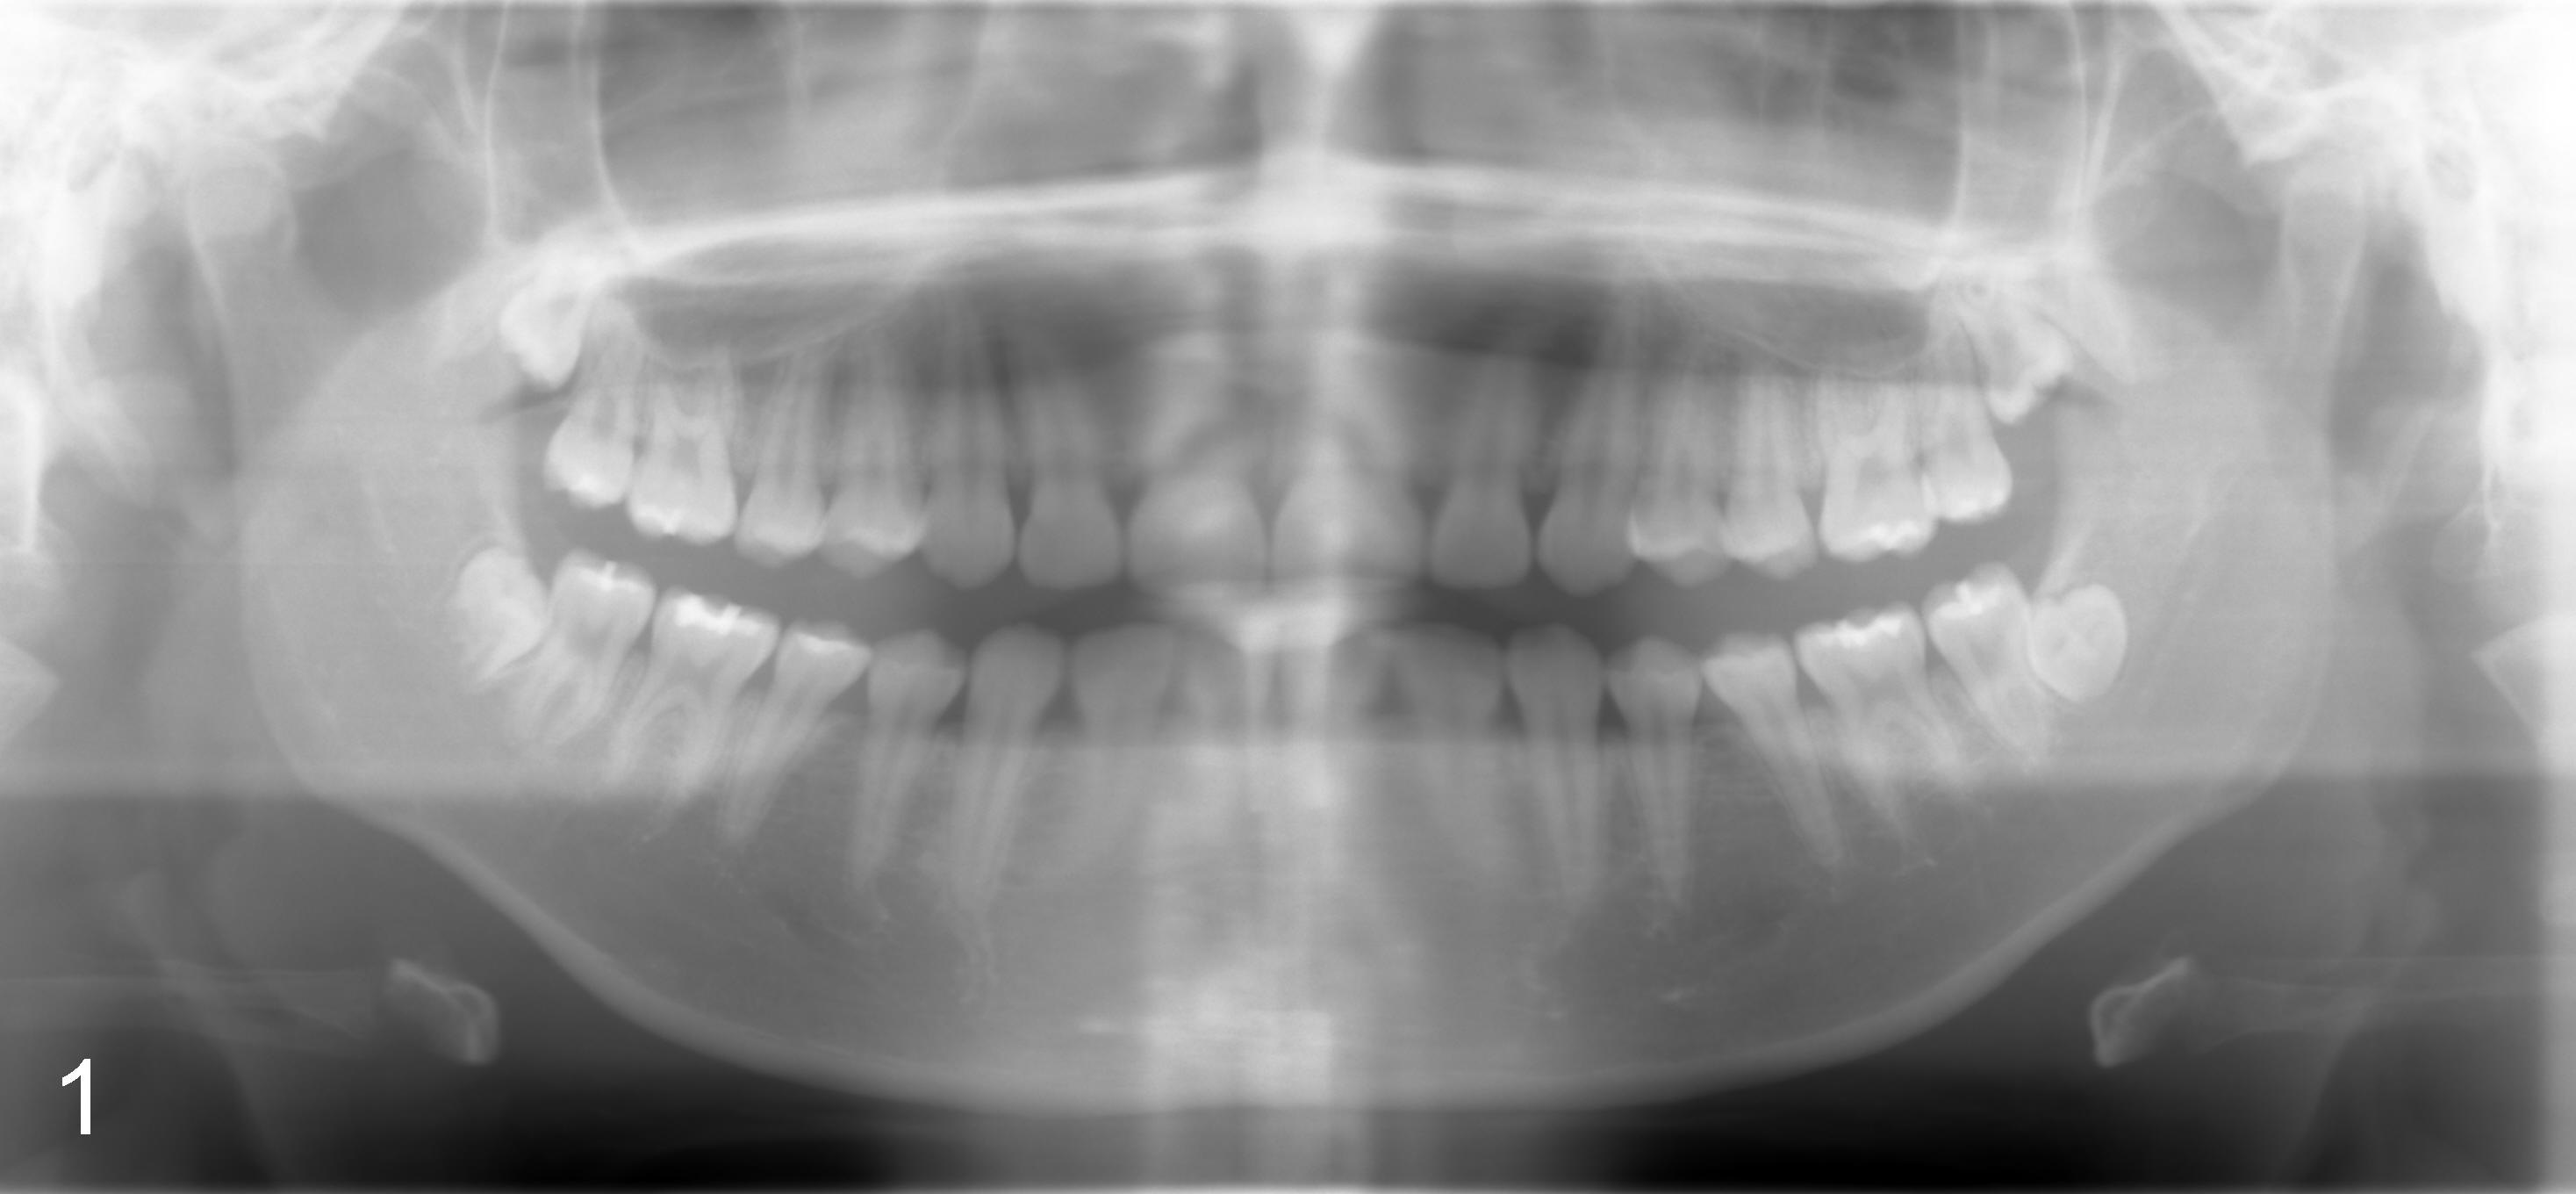

Sixteen-year-old (10 month) Asian female returned to clinic for #32 ext under local anesthesia. Panoramus was taken 2.5 yrs earlier (Fig.1). Surgery includes hockey stick incision, buccal trough, elevator, forceps extraction (Fig.2,3 (B: buccal view, L: lingual)), curettage of tooth bud sac and plain gut suture. Post-op medication consists of Amoxicillin, Lortab and Medrol Dosepak. A month later, the patient returned for #17 with chief complaint (cc) "a lot of swelling after extraction". Surgery and post-op med are the same as for #32 except that the tooth #17 was sectioned several times. The tooth fragments were not saved. It appears that the tooth #17 had yet to develop the roots. Five days after extraction, the patient returned with cc "my lip is still numb". Paresthesia was defined as shown in Fig.4. Vitamin B complex (B1, B12) was recommended. Two days later, she was asked to return for panoramus (Fig.9 as compared to that of pre-op at the same magnification). The bottom of the socket is close to the inferior alveolar canal (IAC). Two weeks post-op, paresthesia was reduced as facial edema subsided (Fig.5), but the patient's main concern was "my lower left teeth (especially incisors) are tender. I cannot chew on the left side". The patient's mother reported that the patient screamed suddenly when she ate. The pain did not subside for two months. Oral and maxillofacial neurosurgeon and cone beam CT were suggested.

How to avoid inferior alveolar nerve injury during third molar extraction? Although the teeth #16 (compare Fig.6 and 7) and #32 (compare Fig.1 vs. 2/3) show more root development in 2.5 years, the socket of the tooth #17 does not appear to separate from IAC (compare Fig. 8/9) probably due to lingual impaction. To avoid nerve damage, control the depth of surgical bur when making buccal trough and/or sectioning the tooth if it has close relationship to IAC. There appears to have been no change in crown relative to IAC in 2.5 years in this case (due to lingual impaction). In addition, update pre-extraction X-ray (panoramus) more frequently for patients under the age of 20 or take CBCT if indicated.